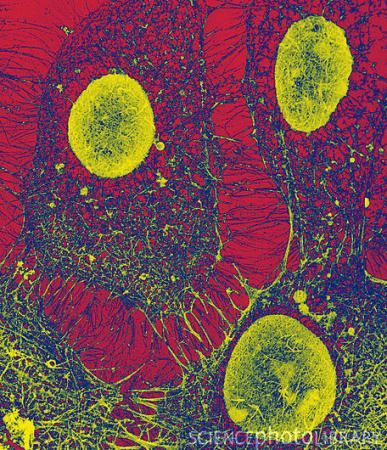

细胞在分子水平上应对外界压力(图)

法国的研究人员最近发现,生物体对饥饿或寒冷环境的成功适应取决于一个名为E2F1 的蛋白质,新成果发表在8月在线出版的《自然—细胞生物学》期刊上。新发现指出了一种重要方法,表明当被暴露在压力环境中时,细胞能够在分子水平上对付处理。